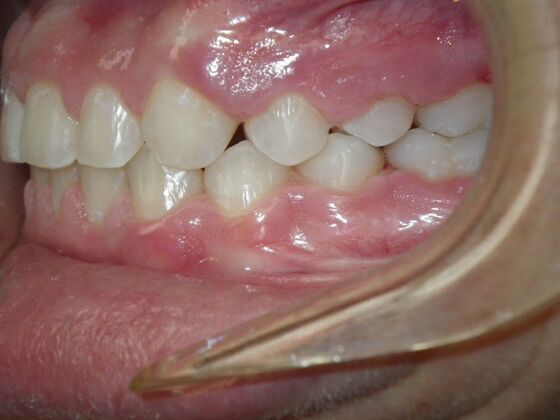

Dylan presented with a functional crossbite in which we used removable expansion appliances for 12 months, followed by bracketing of upper and lower teeth including primary ones to gain alittle more expansion, allowed to wear retainers for 6 months and then followed closely with 6 month ortho recalls and began Phase 2 treatment within 24 months and finished his ortho treatment.